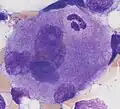

Emperipolesis: Megakaryocyte containing a segmented neutrophil, stained with a May-Grünwald Giemsa stain.

Emperipolesis: Megakaryocyte containing a segmented neutrophil, stained with a May-Grünwald Giemsa stain.